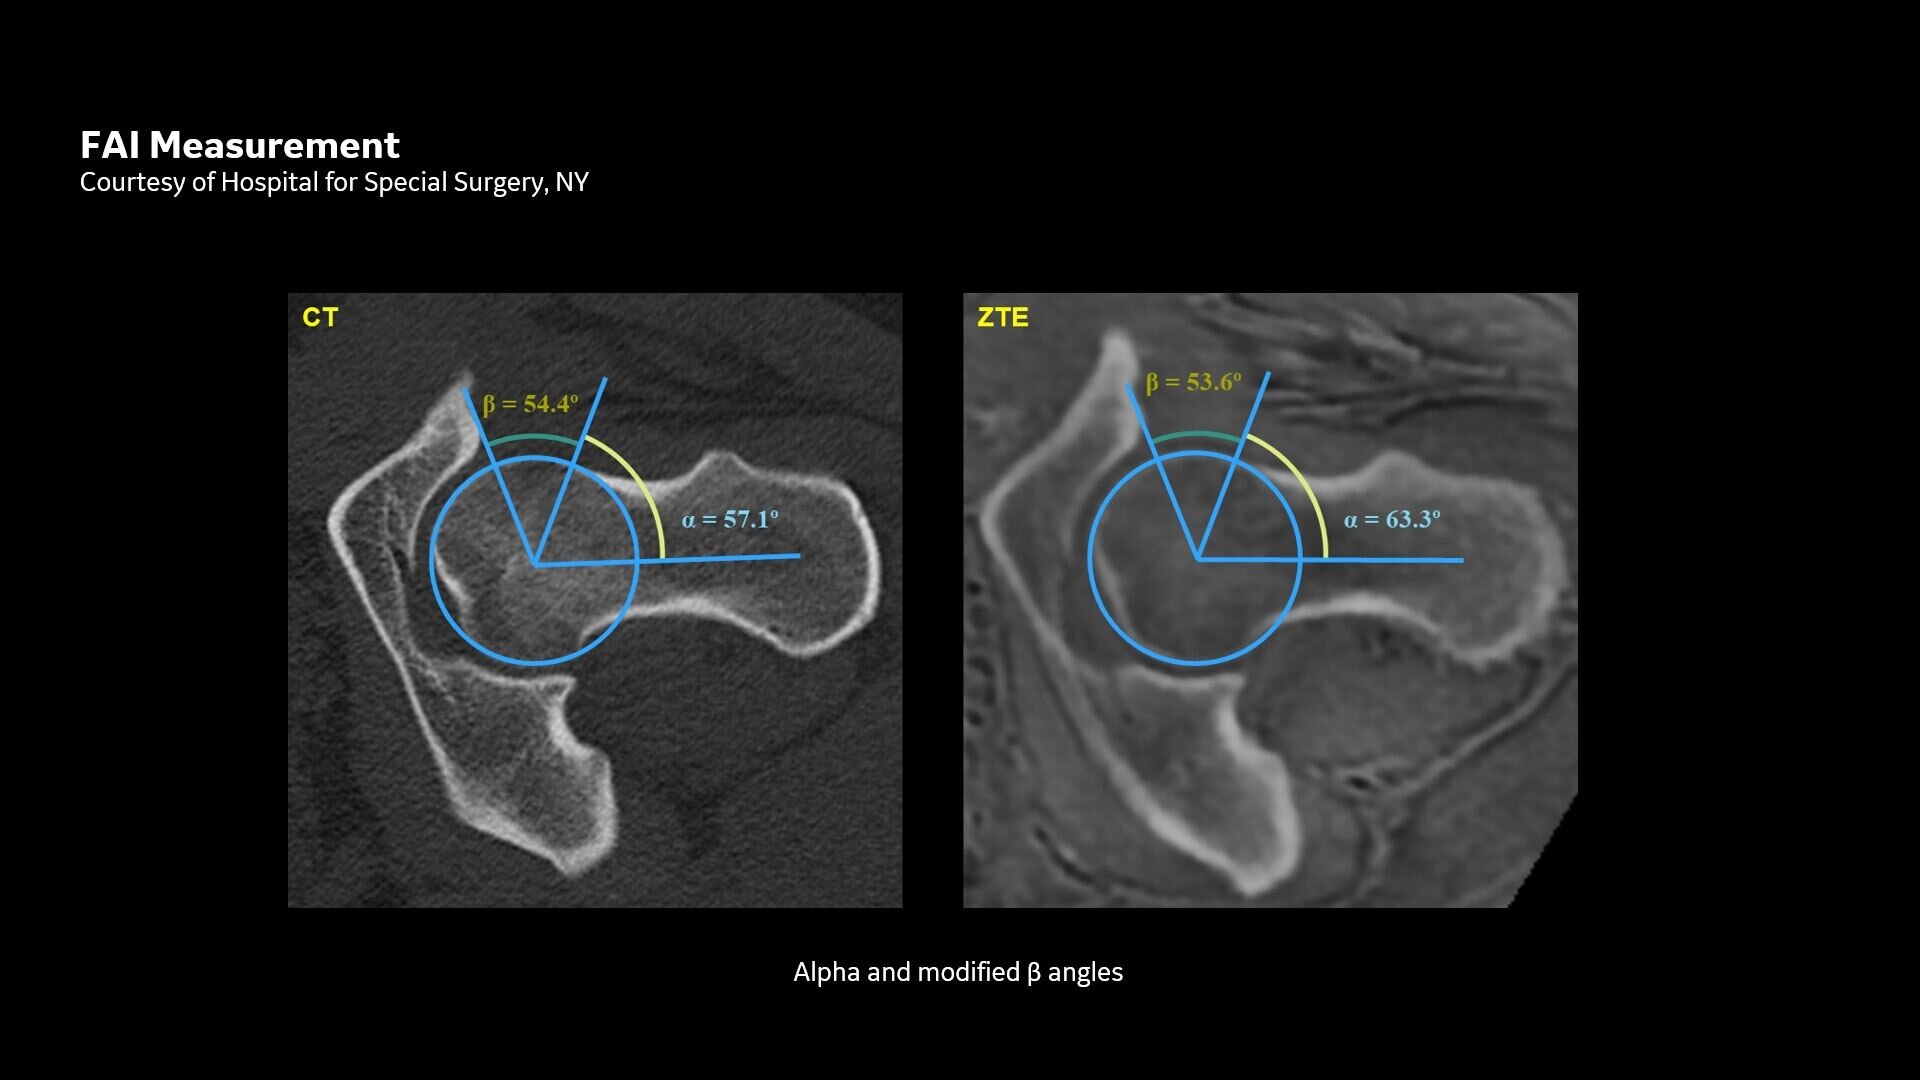

Available for all anatomies without ionizing radiation, oZTEo delivers images of bone morphology, calcification, ossification and fractures. oZTEo complements conventional MR soft tissue exams with perfect co-registration and provides 3D isotropic imaging using a radial ZTE acquisition, with inherent motion insensitivity. Use oZTEo with Volume Illumination for realistic 3D rendering.

CT-like image contrast without ionizing radiation

MR bone imaging provides a CT-like image contrast without ionizing radiation, making it an attractive alternative for pediatric and pregnant patients where ionizing radiation is a concern. In addition, it provides a welcome alternative when longitudinal CTs are required, particularly when low-dose CT systems are unavailable.